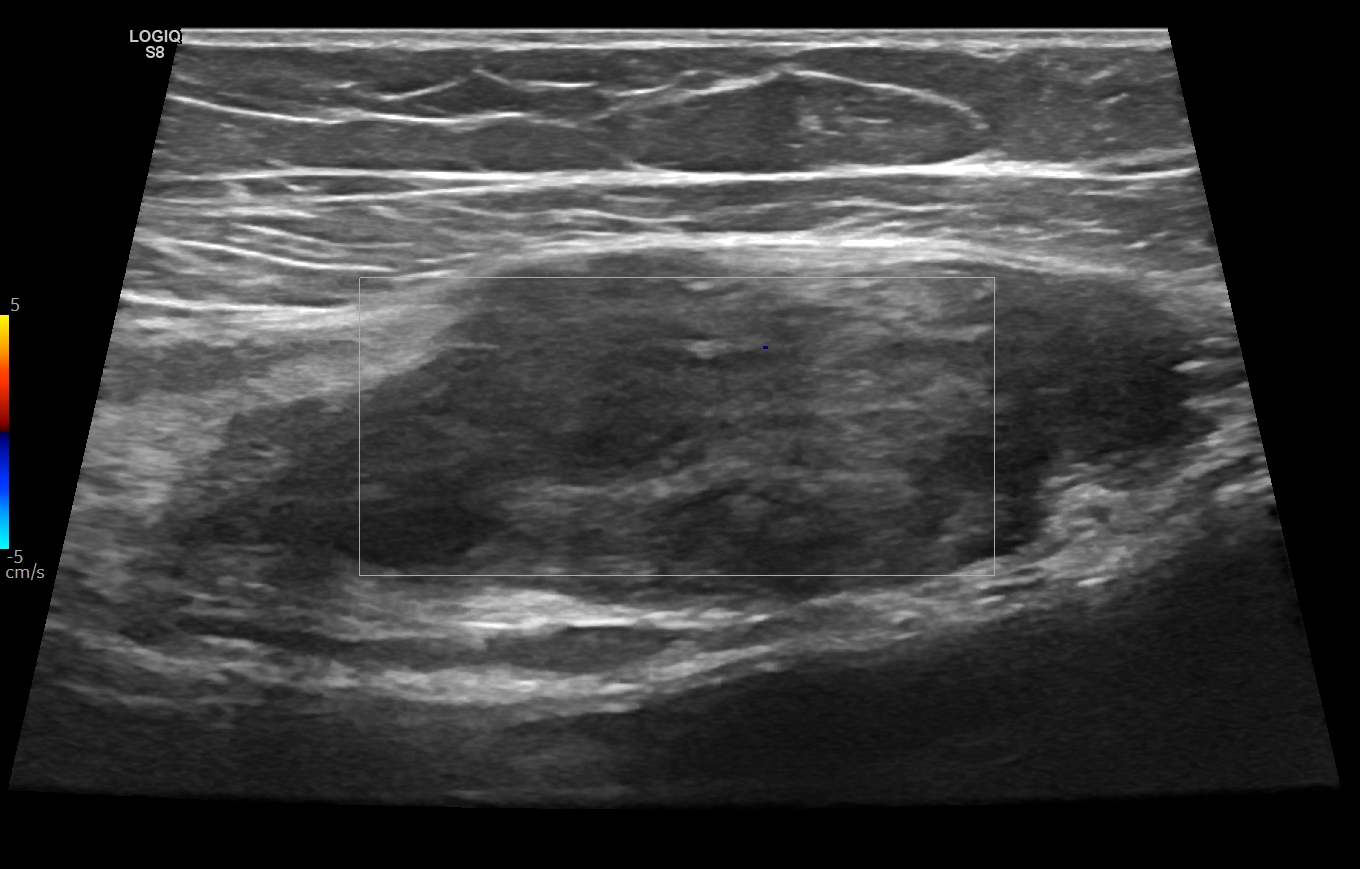

Findings Her entire large bowel was studded with multiple polyps.The rectum and sigmoid had larger polyps as compared to the smaller rest of the bowel which has numerous smaller lesions(Image 1).An ultrasound of her breast was undertaken for the right breasy mass lesion .The ultrasound showed a rather circumscribed lesion in the upper inner quadrant of the right breast splaying fibres of the pectoralis (Black arrowheads in Image 2 ).The lesion was clinically firm to hard and showed no appreciable vascularity on Doppler (Image 3). A USG guided biopsy of the lesion was undertaken which showed spindle cells that were positive for CD99 ,SMA,Desmin and Negative for S100, pan CK, CK 5/6, p63 and CD117,CD 34 . Ki 67 index was less than 3%.(Image 4) . ?eta Catenin showed strong diffuse nuclear positivity(Image 4) . Diagnosis of a spindle cell neoplasm, morphology and immunoprofile favoring Desmoid fibromatosis was given on pathology . Patient eventually underwent prophylactic pancolectomy.She presented a few months post surgery with irregular soft tissue density masses at site of surgical incision on the right rectus (Image 5) and a large intra abdominal mesenteric mass causing distortion and dense bowel adhesions (Image 6). These were diagnosed as fibromatosis on imaging